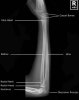

7. Forearm Lateral view(bent/straight arm)